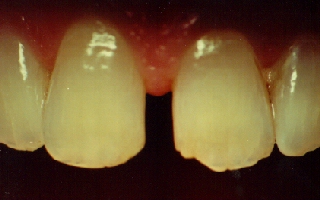

Porcelain Laminates

To Close A Space Between The Two Front Teeth

This patient had a space between his two front teeth. We used the

state-of-the-art technique called porcelain laminates. In this

technique, a small amount (.5mm) of tooth structure is removed from the

front of the teeth and then an impression is taken and sent to a

laboratory. In the lab, space-age porcelain materials are formed into a

very thin piece called a laminate veneer. This porcelain can be formed

and colored to appear incredibly tooth-like. The laminates are then

tried on the tooth and are glued into place with special bonding

materials. Much care is taken to be certain that the two teeth are not

widened too much in proportion to their length in order to give a most

pleasing natural appearance to them. And the smile tells it all! |